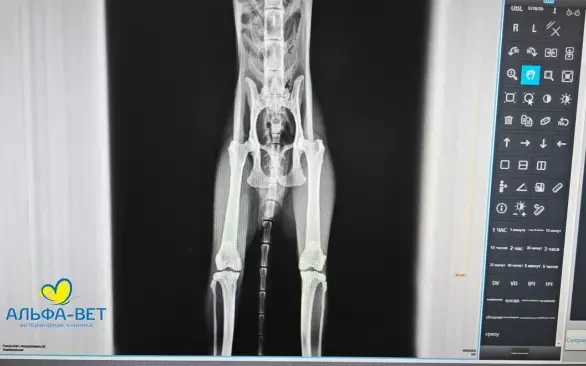

Теоретический материал максимально адаптирован к условиям работы и подкреплен наглядными клиническими случаями. Постоянный режим «Вопрос-Ответ» помогает слушателям быть включенными в процесс обучения.

Участники получили возможность разобрать на практике алгоритм работы с рентгеновскими снимками и их описанием, рассмотрели типовые ошибки. Смогли закрепить на практике основные способы укладки питомцев, чтобы по возможности получать максимально информативные рентгеновские снимки.